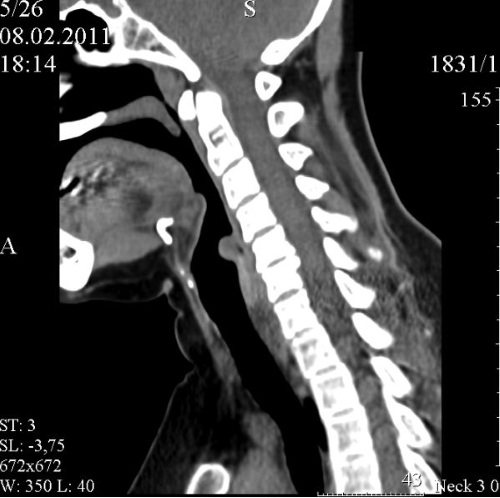

Для диагностики заболеваний глотки и гортани в настоящий момент проводится целый спектр различных исследований. К ним относятся компьютерная томография, ларингоскопия, рентген, МРТ и УЗИ.

КТ

С помощью компьютерной томографии можно рассмотреть каждый слой анатомической области. Является более точным методом диагностики, чем, например, рентген. Может применять с контрастным веществом, оно необходимо для обнаружения злокачественных новообразований, а также контроля лечения.

Позволяет выявить:

- Изменения хрящевой ткани.

- Патологию голосовых связок.

- Опухоли.

- Кисты.

- Полипы.

- Аномалии строения.

- Метастазы раковых образований.